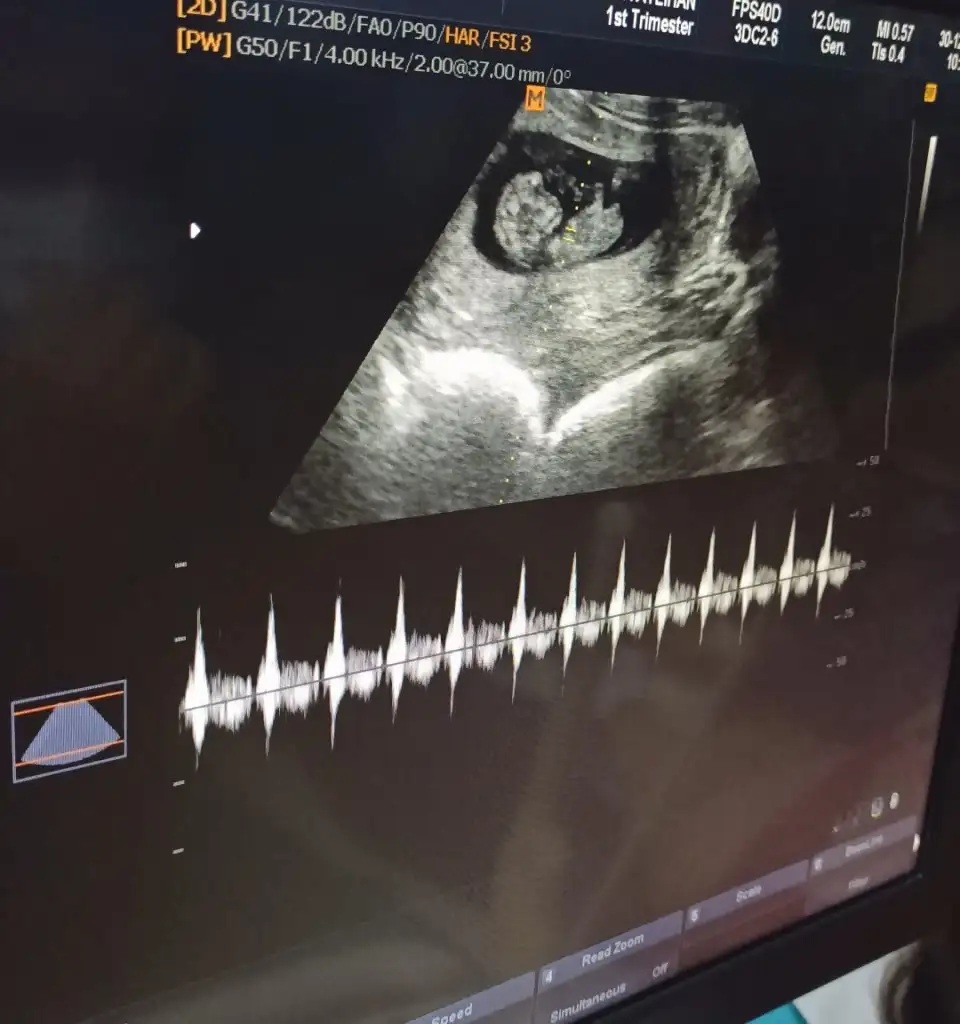

Emin değilim ama sanki erkek gibi başka USG varsa paylaşınMerhaba benimkisi 12 haftalık tam. Bakar mısın lütfen. Doktor 10. Haftada erkeğe benzetti ama bugün de kız gibi dedi :)

Merhaba bende meraktan buralardayımvakit ayırabilirseniz birde bizim tahminde bulunabilirmisiniz

Yükledim hepsini şimdi canım. Nub görünen foto da var.Emin değilim ama sanki erkek gibi başka USG varsa paylaşın